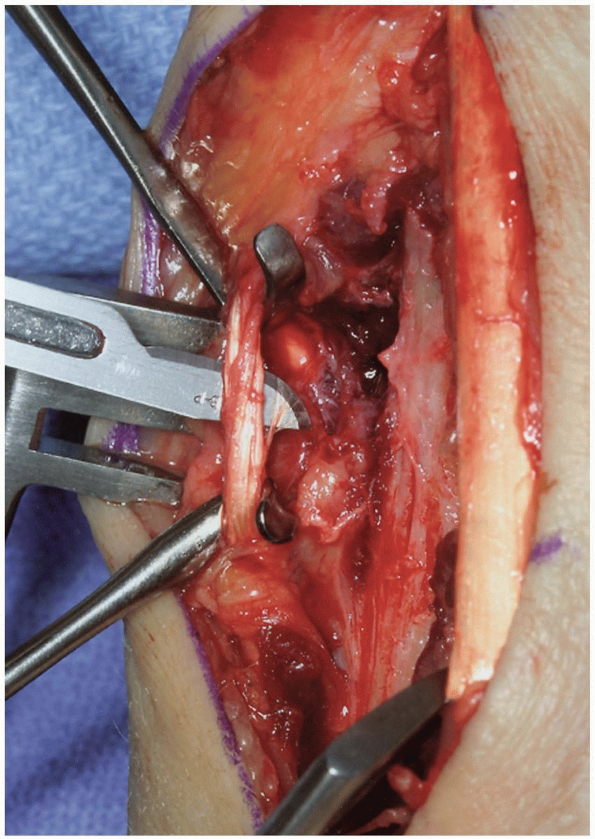

tendons, the retinaculum over the desired compartment is incised. If a

posterior interosseous nerve (PIN) neurectomy is to be performed, a

deeper dissection is made 2 cm proximal to the extensor retinaculum (11) (Fig. 1-4).

The dissection proceeds through the deep fascia of the forearm. The PIN

is identified as it enters the 4th extensor compartment and a 2 cm

segment of the nerve, which is purely sensory at this level, is excised

(11) (Figs. 1-4 and 1-5).

The PIN and posterior interosseous artery course longitudinally from

proximal to distal. Proximally, the PIN innervates the extensor

pollicis longus (EPL) and extensor indicis proprius (EIP). At this

level, it departs from the posterior interosseous artery and travels

distally bound under a fascial layer to the interosseus membrane along

the ulnar border of the radius (4). At the

level of the Lister’s tubercle, the PIN lies adjacent to the ulnar

origin of the 3rd dorsal compartment. It then travels distally with the

anterior interosseus artery across the radiocarpal joint. At the level

of the scapholunate ligament, the PIN branches into its terminal

extensions to bring sensory and proprioceptive nerve fibers to the

capsule and ligaments of the dorsal aspect of the wrist (4).

By denervating the PIN (and anterior interosseus nerve [AIN]), pain

related to the scapholunate ligament and adjacent capsule may be

attenuated.

FIGURE

1-4 The posterior interosseous nerve (PIN) may be exposed for neurectomy by dissection 2 cm proximal to the extensor retinaculum. |

FIGURE 1-5 A,B:

The PIN is identified as it enters the 4th extensor compartment and a 2 cm segment of the nerve, which is purely sensory at this level, is excised to achieve PIN neurectomy. |